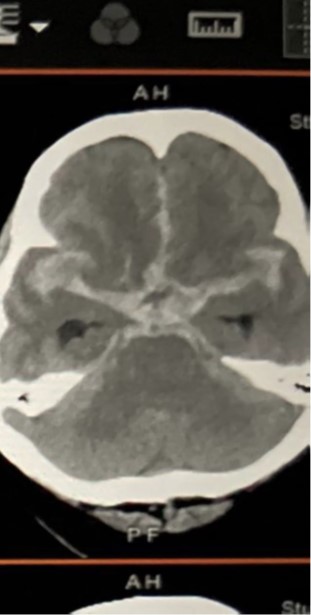

蜘蛛膜下腔出血

蜘蛛膜下腔出血是很嚴重的出血性中風:

- 有1/3患者當場死亡,因為顱內壓急升導致心肺衰竭;

- 另外1/3可到醫院治療但有不同程度的後遺症,最差可變成植物人;

- 只有1/3病人出事後出現少量或沒有後遺症。

所以有以上病徵,要馬上找醫生檢查,延誤診治可導致二次出血,死亡率高達50%。入院後的手術治療只能防止二次出血和可能出現的後遺症,例如腦積水。雖說這病成因不明,但其中多囊腎病患者有較大機會患動脈瘤病。